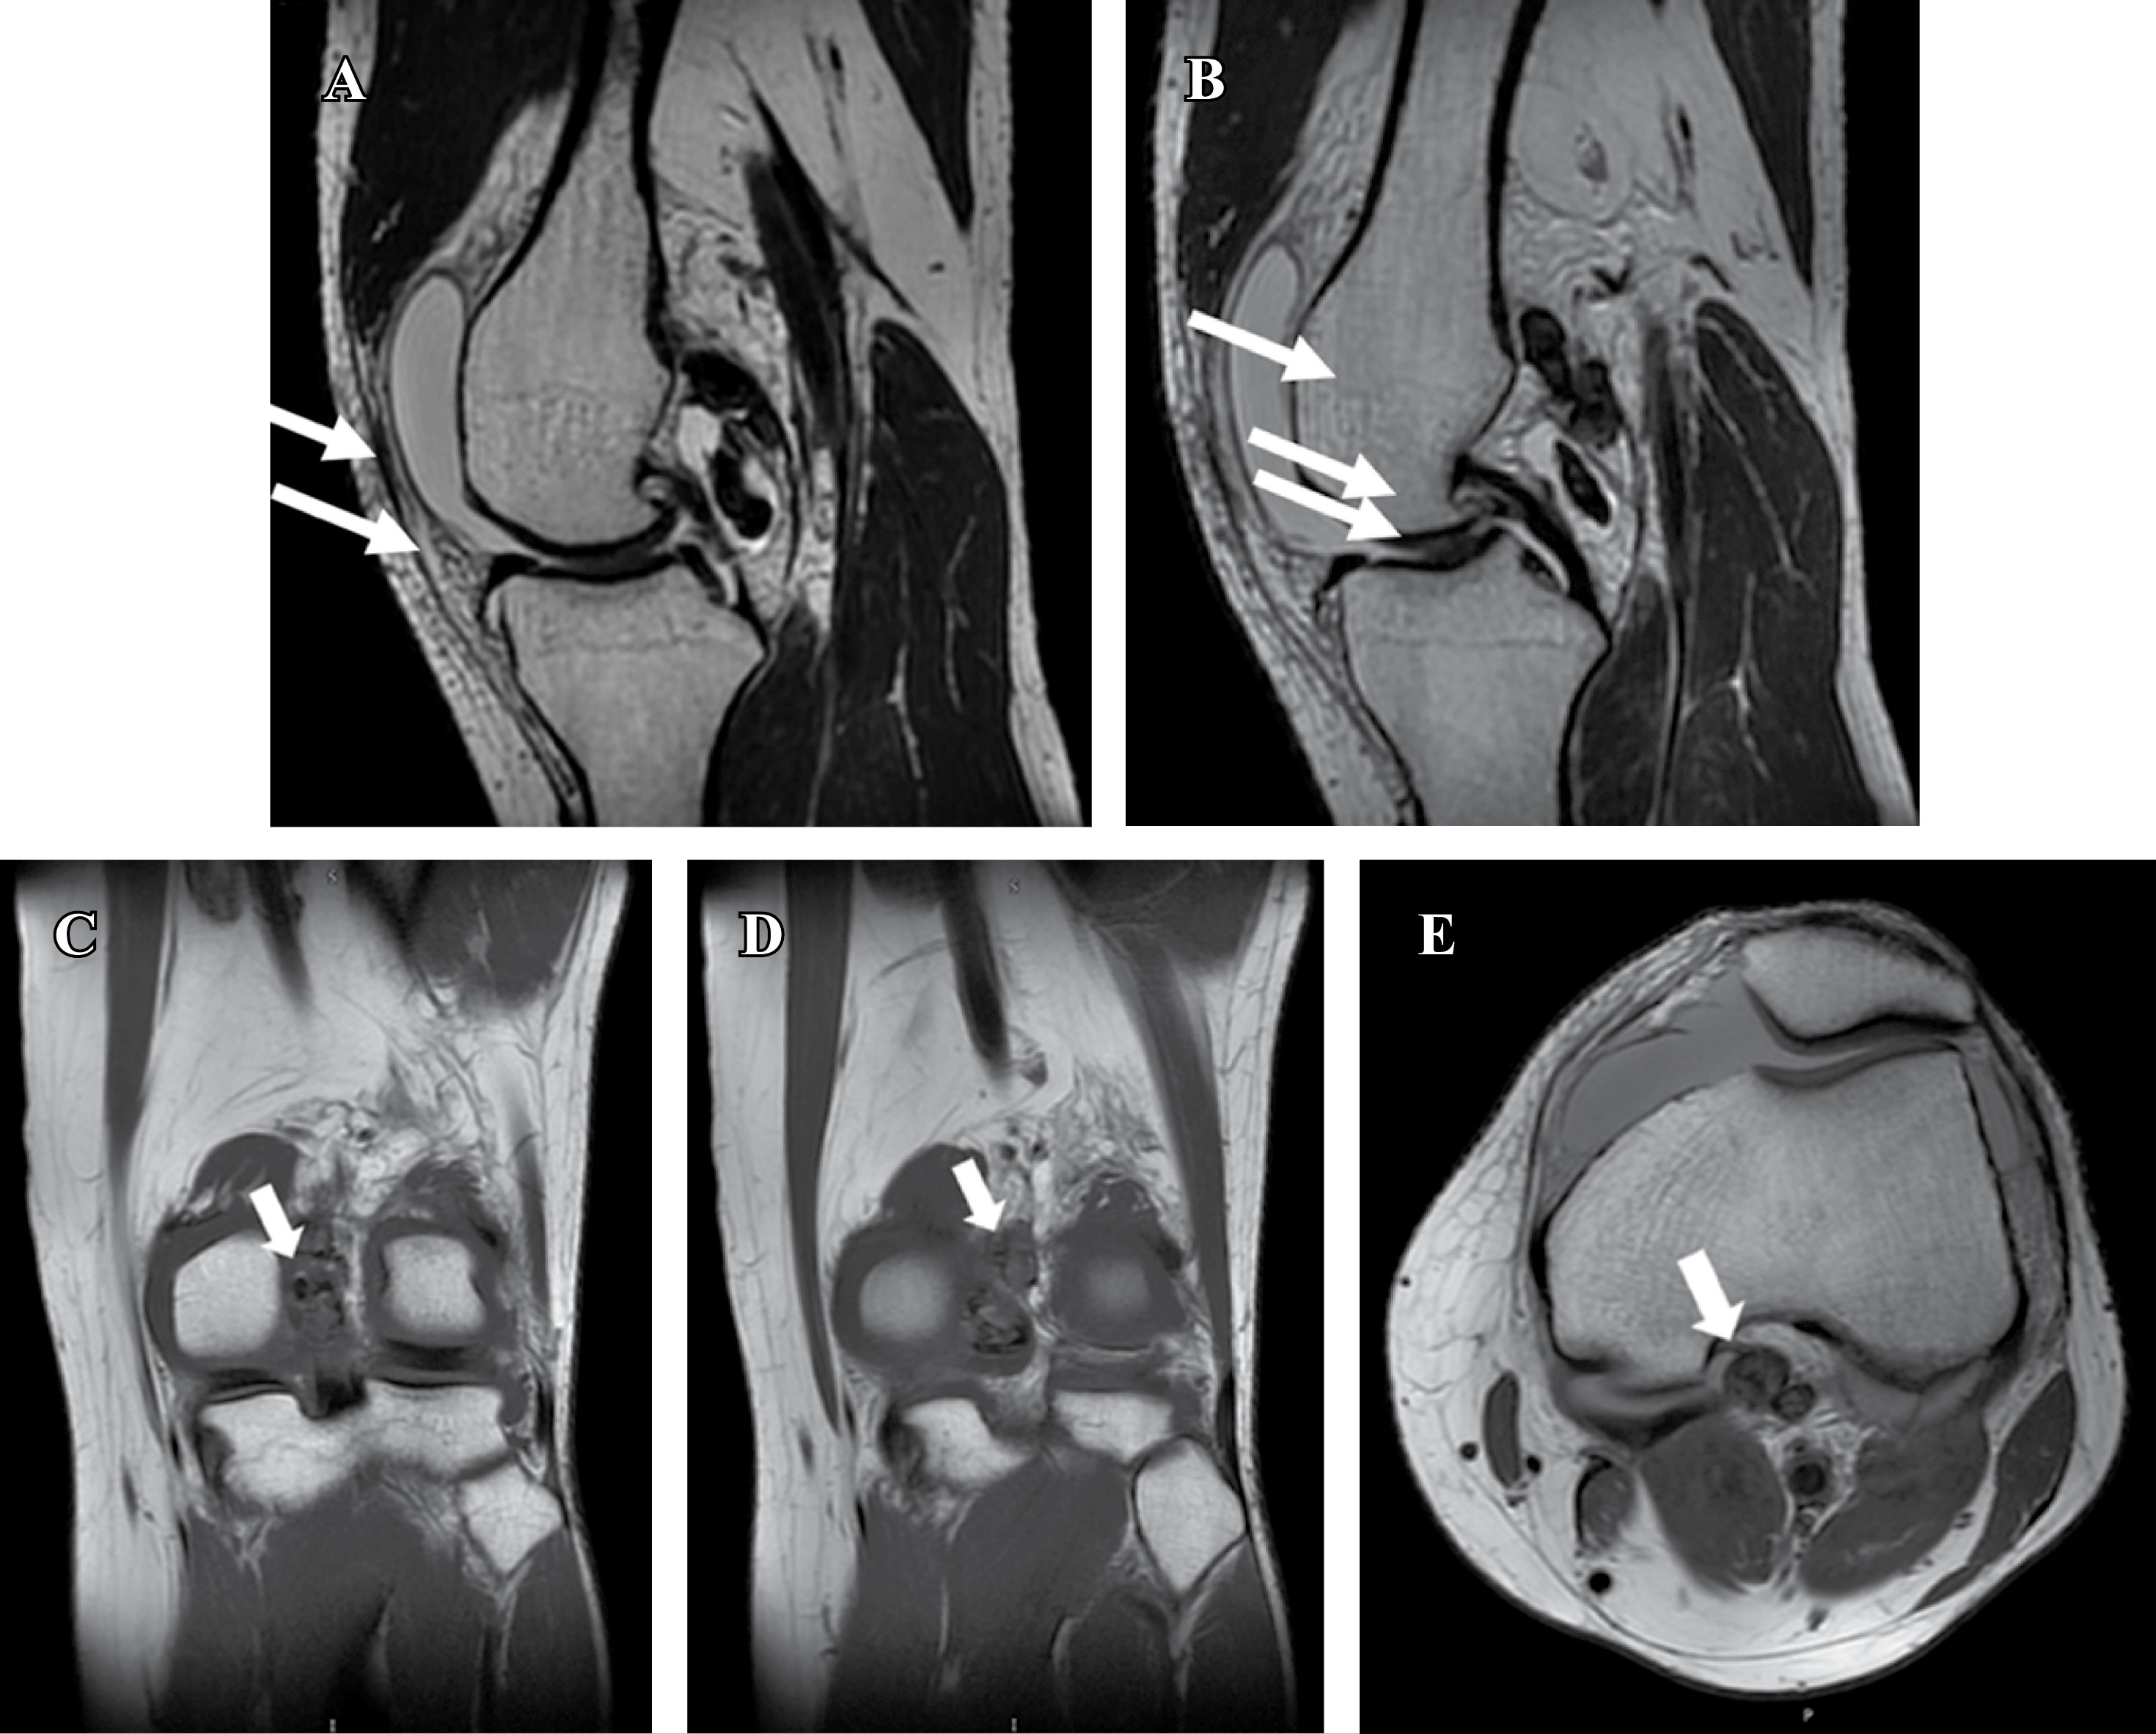

En radiografías anteroposterior (AP) y lateral de rodilla, no se encontraron datos patológicos, por lo que se decidió la realización de una resonancia magnética (RM) simple, en la cual, además de lesión grado I en menisco medial y ligamento cruzado anterior (LCA), se identificó entre la cápsula posterior y el ligamento cruzado posterior al menos cuatro imágenes ovoides, con bordes bien definidos y comportamiento heterogéneo, predominantemente hiperintenso en secuencia de densidad protónica con supresión grasa (Proton Density Fat-supressed Sequence: PD-FS), hipointenso en T1 y T2 y sin señal en la secuencia de susceptibilidad magnética, con un tamaño aproximado de 7 a 20 mm (Figura 1). Se descartó el uso de ultrasonido por tener disponibilidad inmediata de RM.

La RM es el estudio de imagen más útil, indispensable para el diagnóstico y la planificación quirúrgica. En el TGCT localizado intraarticular, las lesiones típicamente presentan en secuencias T1 una intensidad de señal baja a intermedia, con márgenes nodulares o lobulares bien definidos.4 En T2, la señal suele ser baja a intermedia y heterogénea, con áreas hipointensas que corresponden a depósitos de hemosiderina. En las secuencias de eco de gradiente es posible observar el efecto de floración por susceptibilidad magnética, que es casi patognomónico en las imágenes por RM.4,8

Figura 1